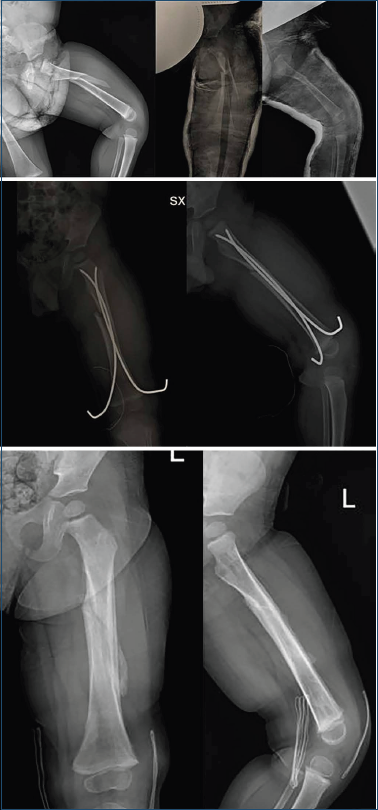

Solo in due casi abbiamo trattato bambini sotto i 5 anni con chiodi elastici, dal momento che con il trattamento incruento la riduzione non è stata ritenuta soddisfacente e con indici di deformità non giudicati tollerabili e compensabili dal rimodellamento osseo (Fig. 5).

Figura 5. Paziente di 4 anni con gesso pelvi podalico, successivo controllo radiografico ritenuto “non accettabile” e successivo shift con chiodi elastici con cui si è ottenuta la consolidazione.